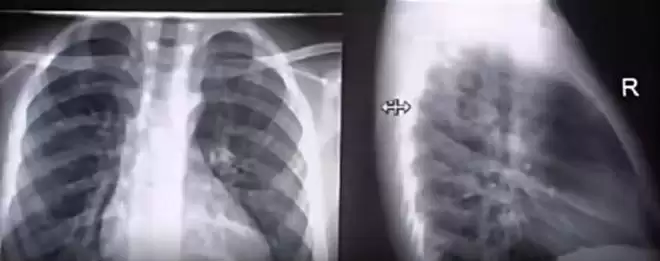

韩国媒体称,泡温泉这个行为,使原本就有心脏疾病的她血管压力上升。当时她的肺部感染也已经开始扩散,两个重要器官的双重伤害之下,这就是她在短时间内心脏发生骤停的原因。

救护车又接到她,将她再次运往附近的医院,但很可惜,在经历了长达14小时的心肺复苏,再加上其他的抢救治疗,大S最终仍旧没有恢复意识,因重度肺部感染和心脏器官衰竭离世。